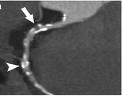

Assessment of stenosis in a coronary artery using dual-source CT.

Overall, researchers said DECT had 92 percent sensitivity and 93 percent specificity, with 93 percent accuracy for detecting any type of myocardial perfusion defect seen on SPECT. Contrast defects at DECT correctly identified 85 (96 percent) of 89 fixed and 60 (88 percent) of 68 reversible myocardial perfusion defects. Compared with angiography, coronary CT angiography had 90 percent sensitivity, 94 percent specificity, and 93 percent accuracy for the detection of more than 50 percent stenosis.